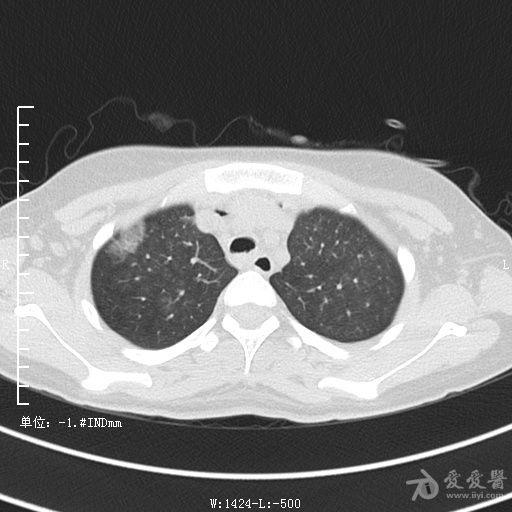

典型支气管扩张及肺水肿CT片

典型支气管扩张肺水肿